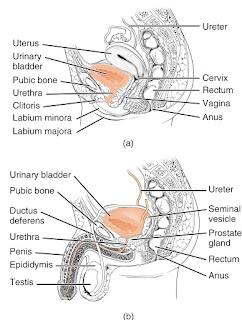

Epididimis

Epididimis adalah organ organ yang berbentuk seperti sosis terdiri atas kaput, korpus, dan kauda epididimis. korpus epididimis di hubungkan dengan testis melalui duktuli eferentes. vaskularisasi epididimis berasal dari arteri testikularis dan arteri deferinsialis. di sebelah kaudal, epididimis berhubungan dengan vasa deferens.

sel spermatozoa setelah di produksi di dalam testis di alirkan ke epididimis. di sini spermatozoa mengalami maturasi sehingga menjadi motil (dapat bergerak) dan disimpan di dalam kauda epididimis sebelum dialirkan ke vas deferens.

Vas Deferens

vas deferens adalah organ berbentuk tabung kecil dan panjangnya 30-35 cm, bermula dari kauda epididimis dan berakhir pada duktus ejakulatorius di uretra posterior.

duktus deferens di bagi menjadi beberapa bagian yaitu ;

- pars tunika vaginalis

- pars inguinalis

- pars skrotalis

- pars pelvikum

- pars ampularis.

pars skrotalis ini merupakan bagian yang di potong dan diligasi saat vasektomi. duktus ini terdiri atas otot polos yang mendapatkan persarafan dari sistem simpatik sehingga dapat berkontraksi untuk menyalurkan sperma dari epididimis ke uretra posterior.

Vesikula Seminalis

Vesikula seminalis terletak di dasar buli-buli dan di sebelah kranial dari kelenjar prostat. panjangnya kurang lebih 6 cm berbentuk sakula-sakula. vesikula seminalis menghasilkan cairan yang merupakan bagian dari semen. cairan ini di antaranya adalah fruktosa, berfungsi dalam menberi nutrisi pada sperma. bersama-sama dengan vas deferens, vesikula seminalis bermuara di dalam duktus ejakulotorius.

Penis

penis terdiri atas 3 buah korpora berbebtuk silindris, yaitu 2 buah korpora kavernosa yang saling berpasangan dan sebuah korpus spongiosum yang berada di sebelah vetralnya. korpora kavernosa di bungkus oleh jaringan fibroelastik tunika albuginae sehingga merupakan satu kesatuan, sedangkan di sebelah proksimal terpisah menjadi dua sebaga krura penis. setiap krus penis dibungkus oleh otot ishio-kavernosus yang kemudian menempel pada rami osis ischii.

korpus spongiosum membungkus uretra mulai dari diagfragma urogenitalis hingga muara uretra eksterna. sebelah proksimal korpus spongiosum di lapisi oleh otot bulbo-kavernosus. korpua spongiosum ini berakhir pada sebelah distal sebagai glans penis. ketiga korpora, yakni dua buah korpora kavernosa dan sebuah korpus kavernosum di bungkus oleh fasia buck dan lebih superfisial lagi oleh fasia colles atau fasia dartos yang merupakan kelanjutan dari fasia scarpa.

di dalam setiap korpus yang terbungkus oleh tunika albuniea terdapat jaringan erektil yang berupa jaringan kavernus (berongga) seperti spon. jaringan ini terdiri atas sinusoid atau rongga lakuna yang di lapisi oleh endotolium dan otot polos kavernosus. rongga lakuna ini dapat menampung darah yang cukup banyak sehingga menyebabkan tegangan batang penis.